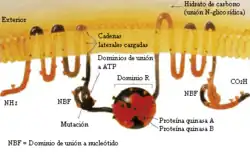

Es producida por una mutación en el gen que codifica la proteína reguladora de la conductancia transmembrana de la fibrosis quística (CFTR). Esta proteína interviene en el paso del ion cloro a través de las membranas celulares y su deficiencia altera la producción de sudor, jugos gástricos y moco. La enfermedad se desarrolla cuando ninguno de los dos alelos es funcional.[1] Se han descrito más de mil quinientas mutaciones para esta enfermedad, la mayoría de ellas son pequeñas deleciones o mutaciones puntuales; menos de un 1 % se deben a mutaciones en el promotor o a reorganizaciones cromosómicas.

Este gen codifica la síntesis de un canal iónico de mil cuatrocientos ochenta aminoácidos, una proteína que transporta iones cloruro a través de las células epiteliales, y que controla la regulación de otros transportadores. En las personas con fibrosis quística, esta proteína está ausente o bien se encuentra en proporciones sensiblemente menores a las habituales.

Biología molecular

Son diversos los mecanismos por los cuales estas mutaciones causan problemas en la proteína CFTR. En particular, la mutación ΔF508, genera una proteína que no se pliega de manera normal y acaba siendo degradada por la célula. Varias mutaciones comunes en la población askenazí dan lugar a la síntesis de proteínas demasiado cortas, a causa de una conclusión anticipada de su producción. Otras mutaciones menos frecuentes originan proteínas que no utilizan la energía como es debido, no permiten que el cloruro cruce la membrana apropiadamente, o son degradadas a una tasa más rápida que la normal. La deficiencia en el transporte de cloro hace que las células no expulsen agua al exterior y por lo tanto el moco sea más espeso. Ciertas mutaciones pueden conducir también a una merma en la producción de copias de la proteína CFTR.[8]

Estructuralmente, el gen CFTR pertenece a la denominada superfamilia de transportadores ABC (acrónimo para el inglés ATP Binding casete, "casete de unión a ATP").[8] La estructura terciaria de la proteína codificada por este gen, consta de dos dominios capaces de hidrolizar adenosín trifosfato, lo que permite a la proteína utilizar energía en la forma de ATP. Asimismo, otro par de dominios, cada uno constituido por seis hélices alfa, posibilita el paso de la proteína a través de la membrana celular. La activación se concreta por reacción de fosforilación en un sitio de unión regulador, sobre todo mediante la proteína quinasa A (PKA, EC 2.7.11.11—antes denominada cAPK o proteína quinasa dependiente del adenosín monofosfato cíclico).[8] El carboxilo terminal (C-) de la proteína está unido al citoesqueleto por interacción con dominios proteicos PDZ.[33]